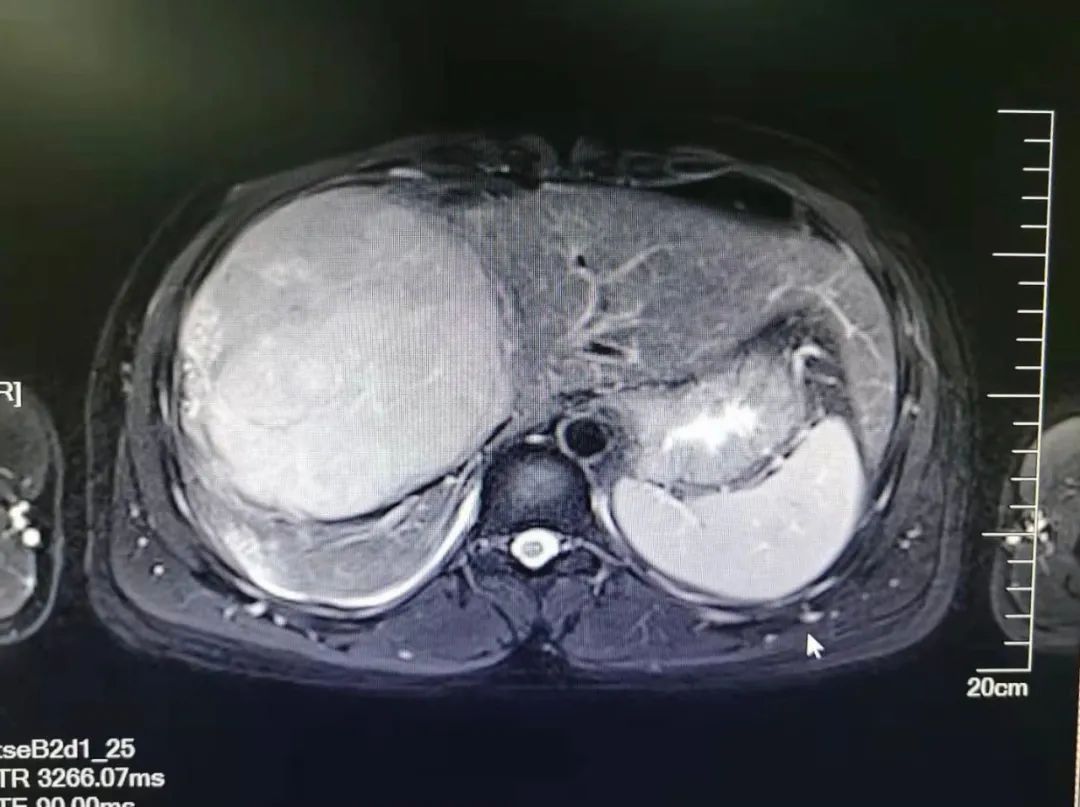

据磁共振显示,患者肝肿瘤已侵占肝脏80%,剩余肝脏已被挤成月牙形,并且肝癌合并门静脉癌栓,术中除了要切除右三叶肝脏、切开门静脉,完整取出癌栓,还有保证剩余肝体积足够患者生存,手术完整切除很易造成肝静脉、腔静脉、肝动脉损伤,出现大出血,肝功能衰竭。手术风险大,术中出血多,但是如果不做手术,患者可能只有两三个月生存期。一个巨大的难题摆在医生、患者和家属面前!

在郑永主任医师带领下,手术如期进行,进入腹腔后发现手术难度比术前预想的还要大。患者肿瘤占据了整个右上腹,局部的肿瘤增生血管像蜘蛛网一样布满整个上腹部,成了一个个拦路老虎。右上腹基本无一丝手术操作空间,手术难度大,对术者技术要求特别高。面对这一情况,手术团队精诚合作,按预期计划进行,术中前入路切除了右肝巨大肿瘤,打开了患者门静脉,完整取出癌栓组织!